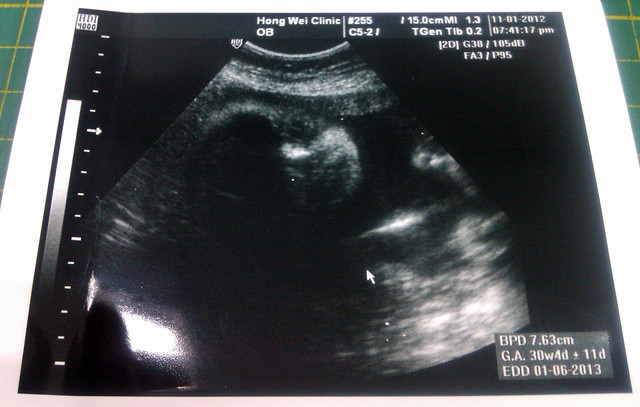

預估週期為30週又4天囉...

目前妞妞預估是30W+4D,重量約1700g,重量值比姐姐之前好一點

而超音波的圖片,剛好拍到妞妞正在看我們耶...

圖片拿遠一點看應該就能看的滿清楚的吧